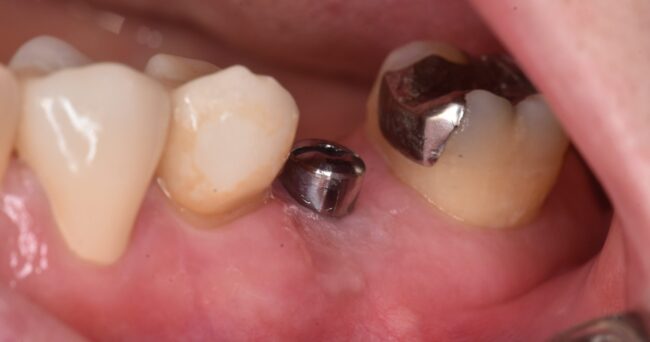

これは金歯です。金歯なので保険適応ではありません。一昔前の最高の治療と言えば、金を用いた治療を指していました。今でも、きちんと治せば、長年問題がなく使えるもの、という認識で間違いありません。

金のメリットは、金合金も何種類もあるのでどれに選ぶかにもよりますが、基本的には歯の強度よりも弱いので、噛みあっている歯を壊さないこと、延性・展性(伸びる性質)に優れているため、縁が合わなくてもすり合わせることで空間をふさぐことができ、上のような複雑な形で内側を保護する能力に優れる=虫歯の再発率が低い、ということです。

ゴールドについての可否は一度置いておき、この処置がどうなっていたのか?を見ていこうと思います。

上の部分を除去するとこのような状態でした。